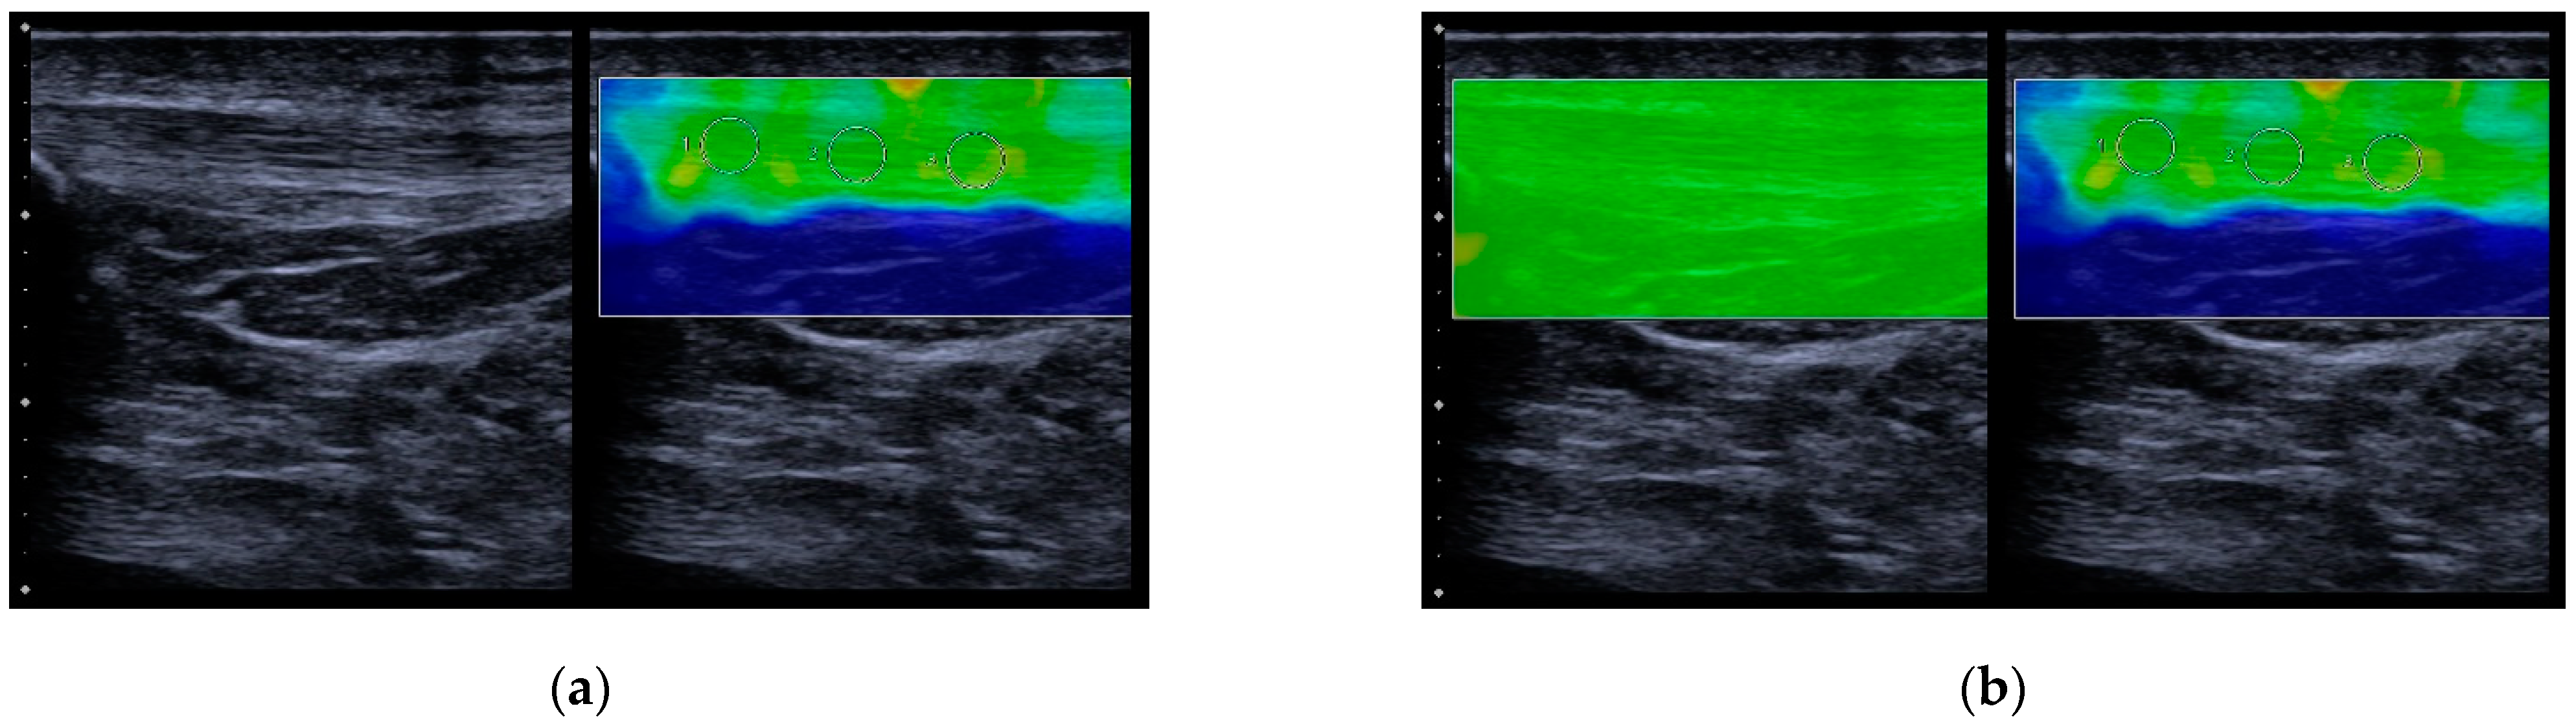

2.2. SWE Examination Protocol